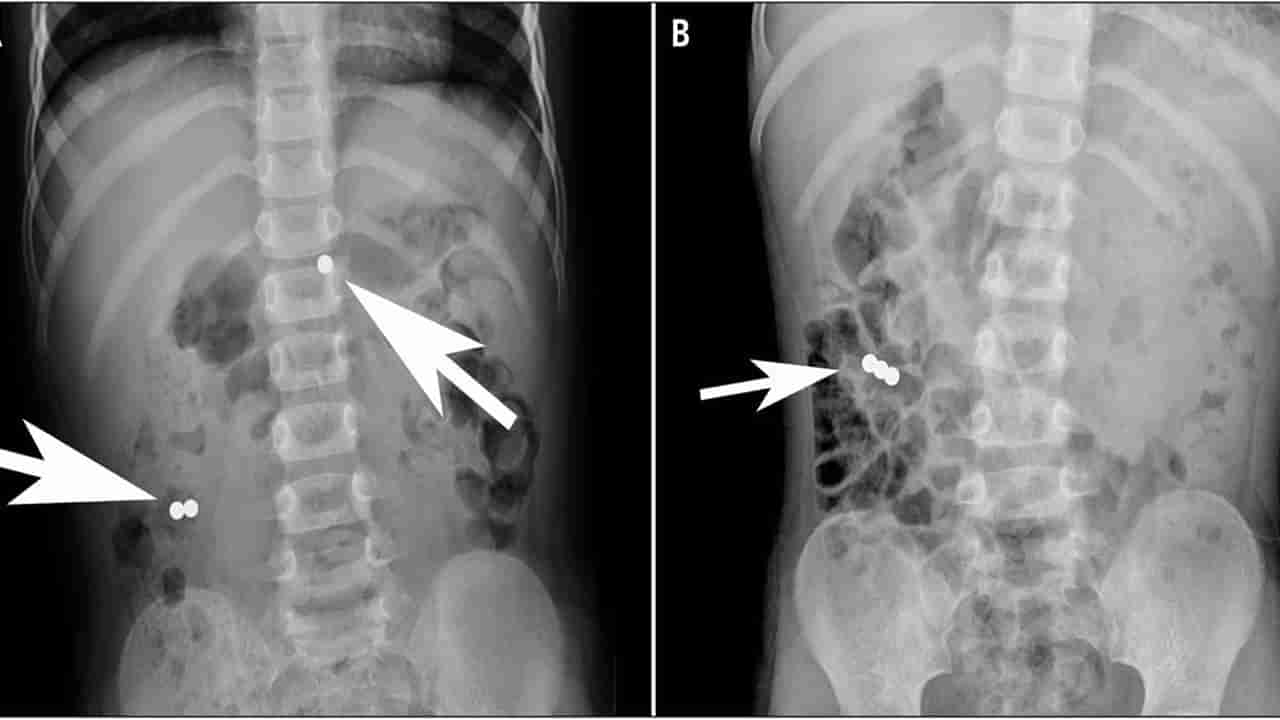

ఫిబ్రవరి 10వ తేదీన బిన్హొ సిటీలో నివాసముంటున్న డికా అనే రెండేళ్ల చిన్నారి తీవ్రమైన కడుపునొప్పితో ఆస్పత్రిలో చేరింది. అక్కడున్న డాక్టర్లు సదరు చిన్నారికి ఎక్స్రే, అల్ట్రాసౌండ్ తీయగా.. కడుపులో ఏవో వస్తువులు ఉన్నట్టు గుర్తించారు. హుటాహుటిన ఆమెకు ఎండోస్కోపిక్ సర్జరీ చేశారు. కడుపులో నుంచి 11 అయస్కాంతాలు తొలగించడంతో పాటు.. పేగుల మధ్య ఇరుక్కుపోయిన మరో 8 అయస్కాంతాలను తీశారు. ఇక డుయోడినమ్ దగ్గర ఉన్న చిన్న ప్రేగులోకి ఇరుక్కుపోయిన మరో 8 అయస్కాంతాలను తొలగించి చిన్నారికి కుట్లు వేశారు డాక్టర్లు. దాదాపుగా 3 గంటల పాటు సాగిన ఈ శస్త్రచికిత్సతో మొత్తం మొత్తం 27 అయస్కాంతాలను తొలగించి.. అమ్మాయికి పునర్జన్మను అందించారు డాక్టర్లు.